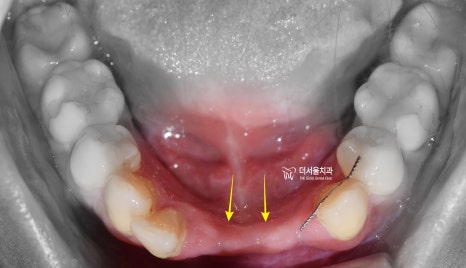

1. 초진 사진

과거에 교정치료를 받으셨으나,

사진에서 볼 수 있는 것 처럼

치열이 많이 흐트러진 것을

알 수 있으면서 고정형 유지장치도

떨어져 있는 것을 볼 수 있습니다.

상악 및 하악 둘 다,

치열의 개선이 필요한 상태이며

특히 하악의 경우 치아가 빠진지

시간이 상당히 오래 흘러서

치조골 및 연조직(잇몸)의 퇴축이

관찰되면서 인접치아들이 앞쪽으로

일부 이동이 된 것을 볼 수 있습니다.

더불어, 뼈가 많이 위축이 되어서

골 폭의 및 잇몸이 많이 얇아진 것을

볼 수 있기 때문에

여기에 임플란트를 심을 때는

상당히 신중해야 되겠습니다.

교합 상태 또한 조정이 필요합니다.